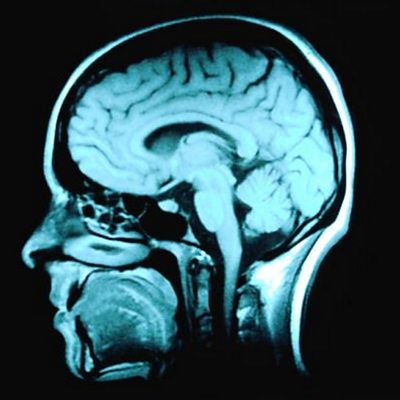

Geoff Watts meets researchers trying to find a new way to fight depression by studying those who never get it. In the second of two programmes Geoff meets scientists at the University of Manchester, studying the brains of people who have undergone traumatic life events without becoming seriously depressed and comparing them to the brains of those people who do. The hope is that new psychological therapies or even preventative medications might be developed to treat the one in five people who will at some point in their lives, become clinically depressed. (Image: MRI scan of the head and brain. Credit: Corbis Royalty Free)